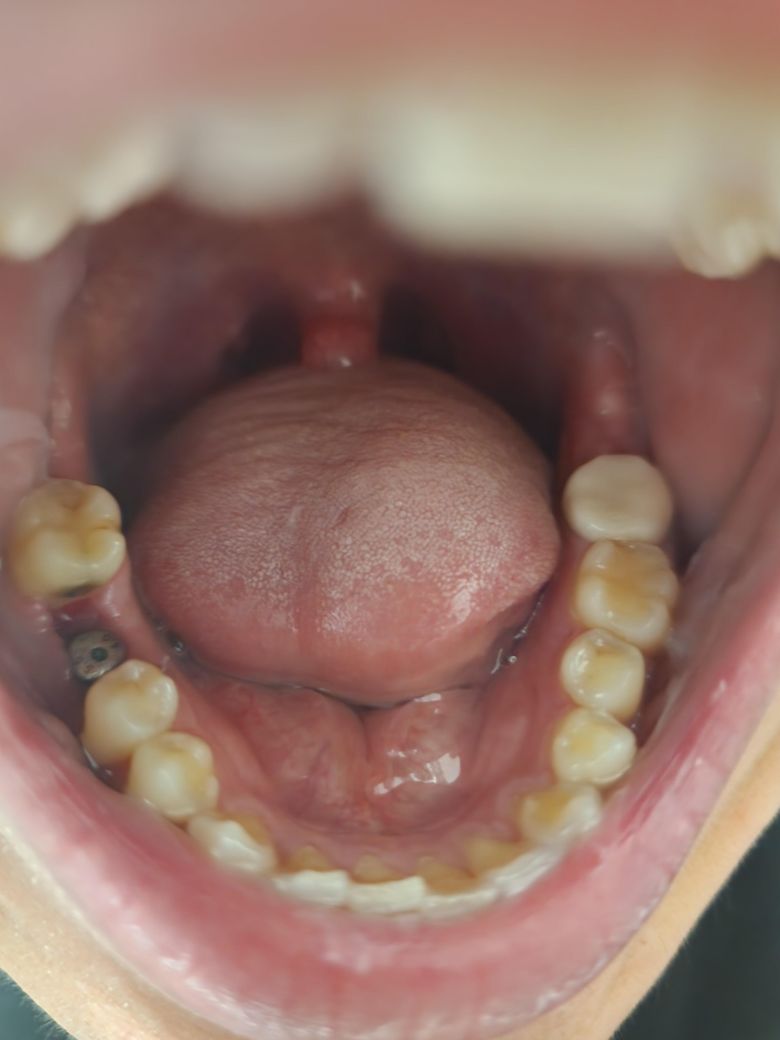

제가 어제 날짜인 5월20일날 왼쪽 아래 어금니 지르코니아 크라운에 문제가 있어 재제작하려고 기존에 있던 크라운빼고 다시 본떳고 현재 임시치아 부착상태이고요 오른쪽 아래 어금니는 사진에서 보시다싶이 5월3일날 발치 후 즉시 뼈이식 임플란트 한 상황입니다..그런데 어제 치위생사가 임시치아쪽으로는 음식 씹지말래서 오른쪽 뼈이식 임플란트한 수술부위로 조심히 씹고 사진에서 보이는 나사?부분도 조심히 칫솔질 해도된다는데 이게 정말 맞는건가요??뼈이식 임플란트 한지는 정확히 18일차인데 수술부위 아직 잇몸도 차오르지 않고 아물지도않고 구멍이 있는데 식사를 해도된다는게 맞는건지요ㅡㅡ??요즘 치아때문에 지금 삶의 질도 떨어지고 우울하네요.....어떻게 식사를 해야하고 대체 어느쪽으로 저작을 해야될까요?ㅜㅜ제발 답변부탁드립니다 긴글 읽어주시느라 너무 감사드립니다....

• 1번 째 사진